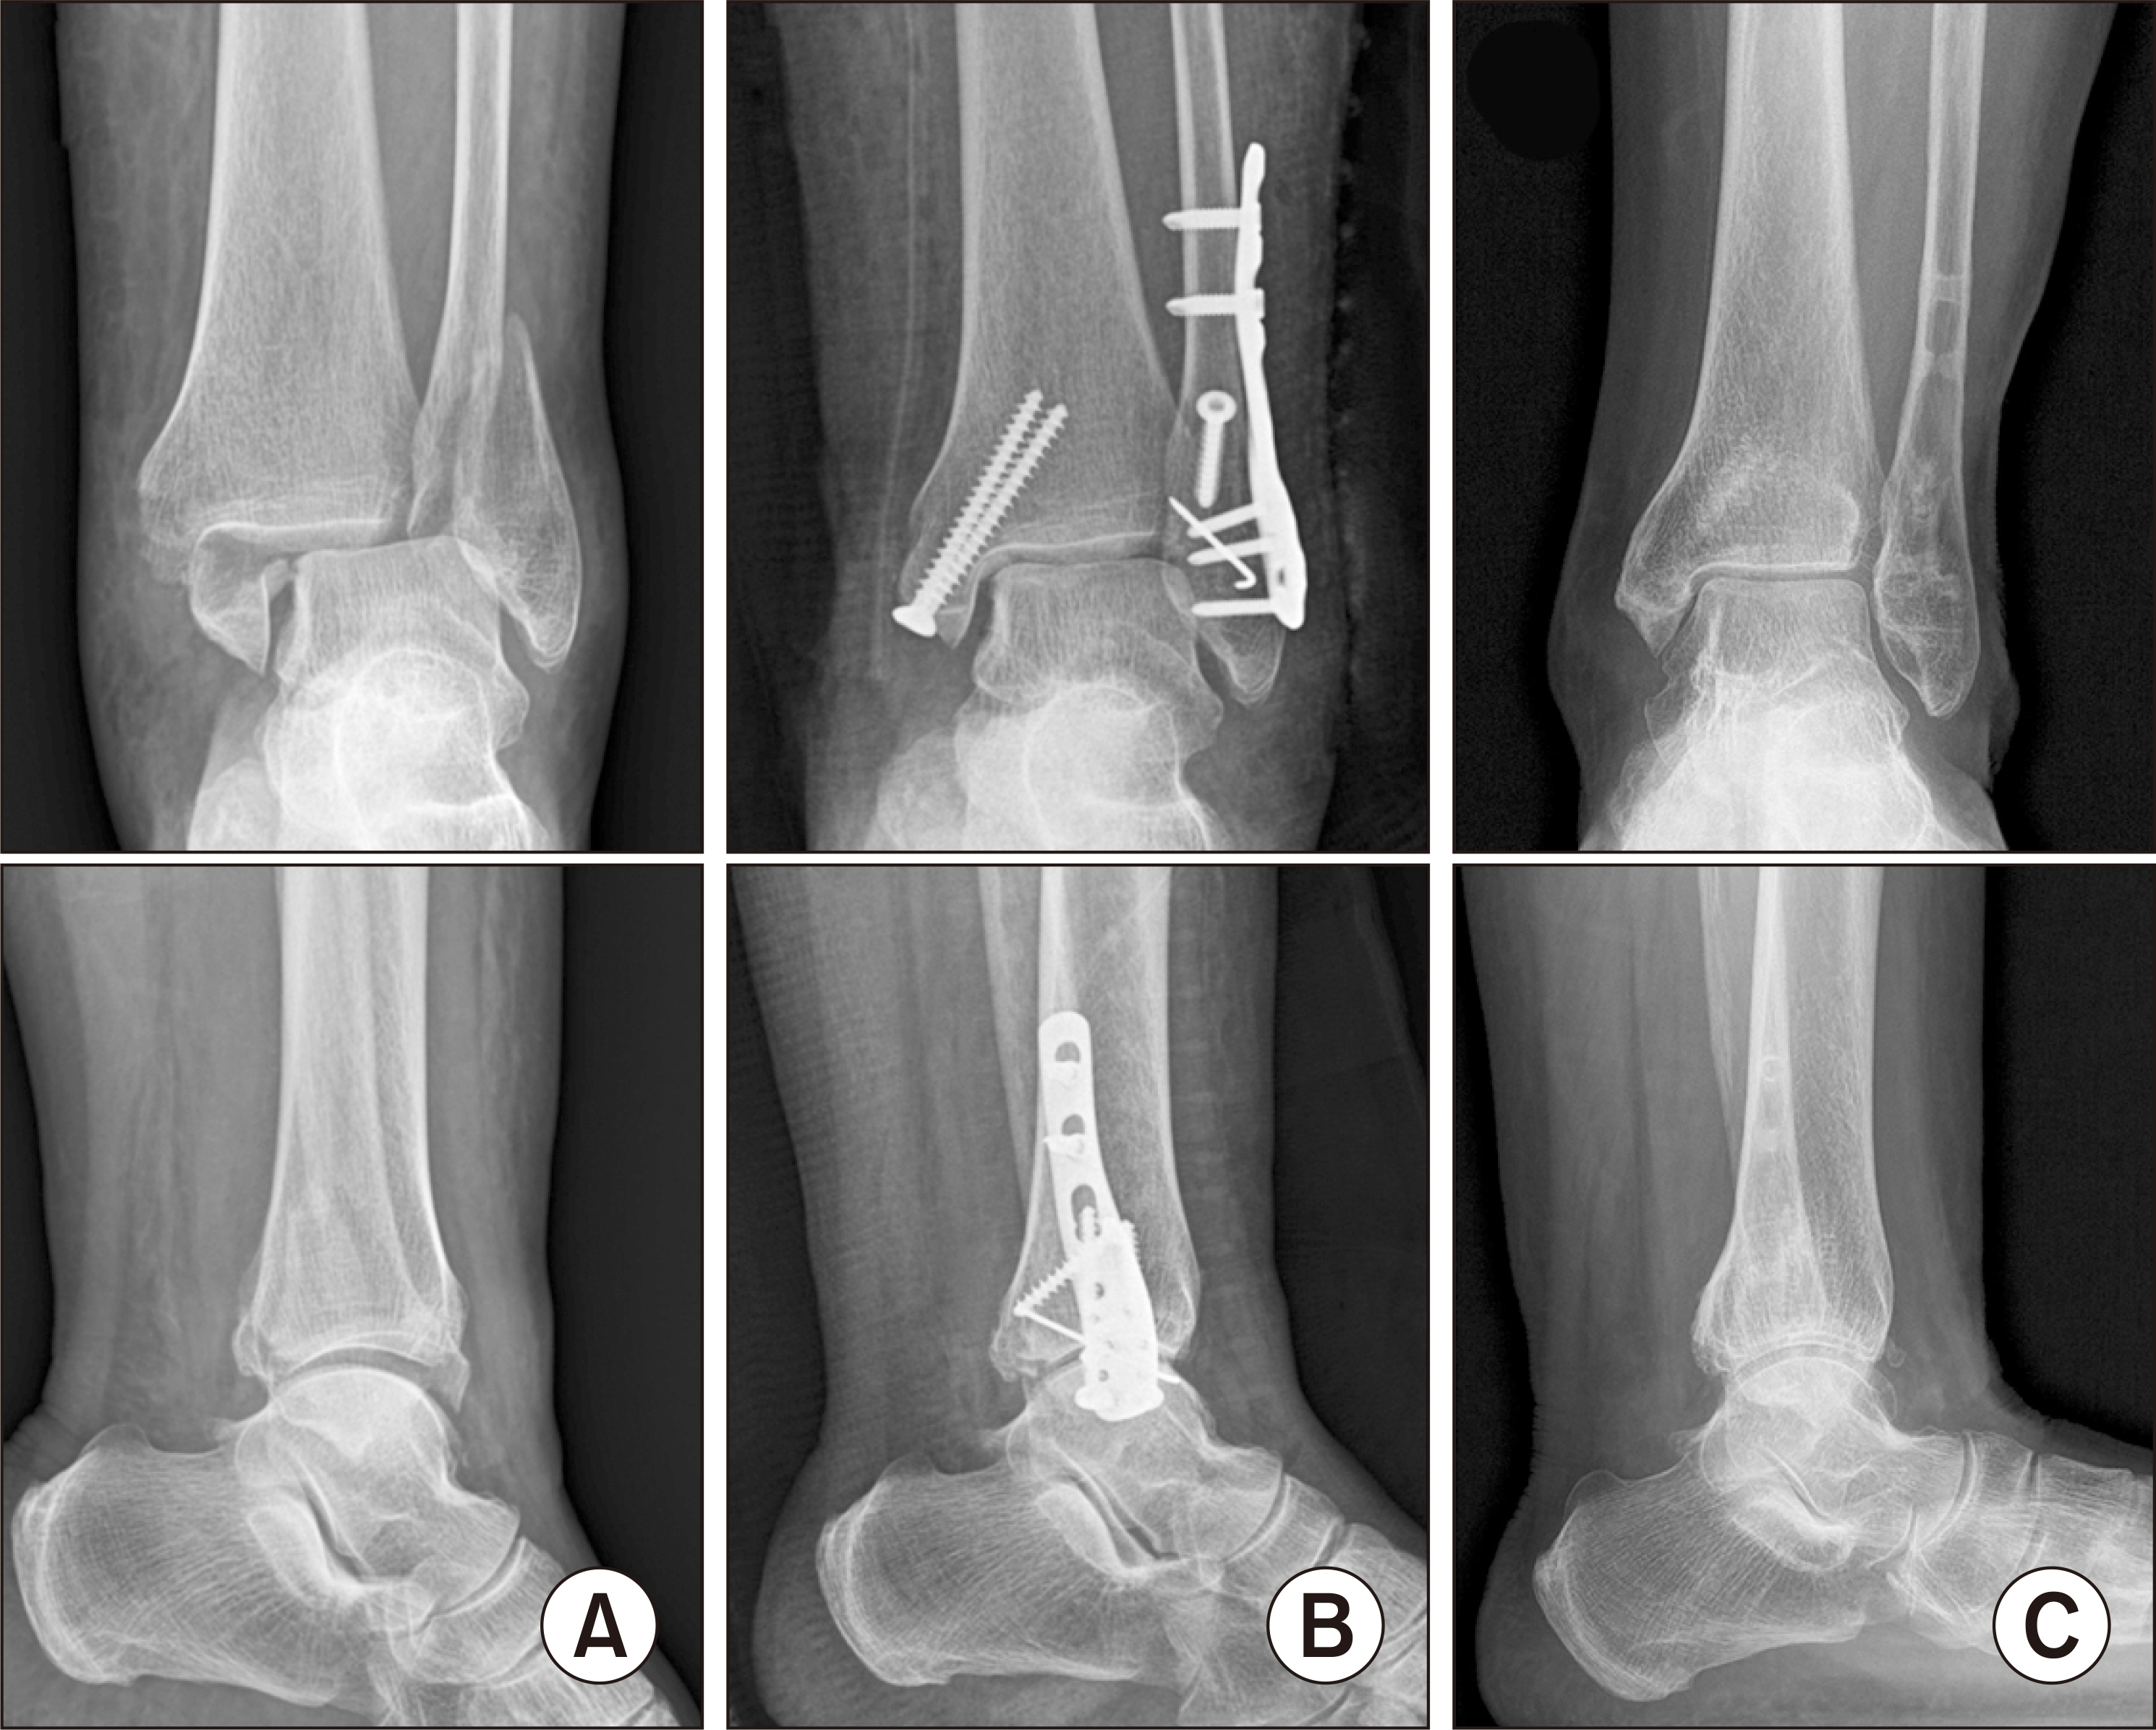

Comparison of Outcomes Using Cortical Lag Screws Versus Cancellous Position Screws for Fibula Fixation in Weber Type B Rotational Ankle Fractures

Ankle fractures are common in the orthopedic field. Lateral malleolar fractures are often treated with lag screws and locking plates. Cortical screws are typically used as lag screws to achieve absolute stability through compression. In osteoporotic bone, however, achieving sufficient compression with cortical screws can be challenging. Cancellous screws may offer better fixation in metaphyseal bone. This study compared the outcomes of using cortical screws as lag screws and cancellous screws as position screws for lateral malleolar fixation.

This retrospective study included patients who underwent surgery for Weber type B ankle fractures at the authors’ hospital between March 2019 and March 2022. The patients were divided into two groups based on the screw type: cortical lag screws (n=70) and cancellous position screws (n=35). In both groups, a locking plate was applied in the same manner after screw fixation. The outcomes were evaluated using the visual analog scale (VAS), Olerud-Molander score (OMS), foot and ankle outcome score (FAOS), and foot function index (FFI). Complications, such as fixation failure, nonunion, and malunion, were recorded.

For the fixation of Weber B fibular fractures, cortical lag screws and cancellous position screws showed comparable clinical outcomes. Cancellous screws with plate fixation may offer a viable alternative in cases with poor bone quality or difficulty applying lag screw techniques.

Figure